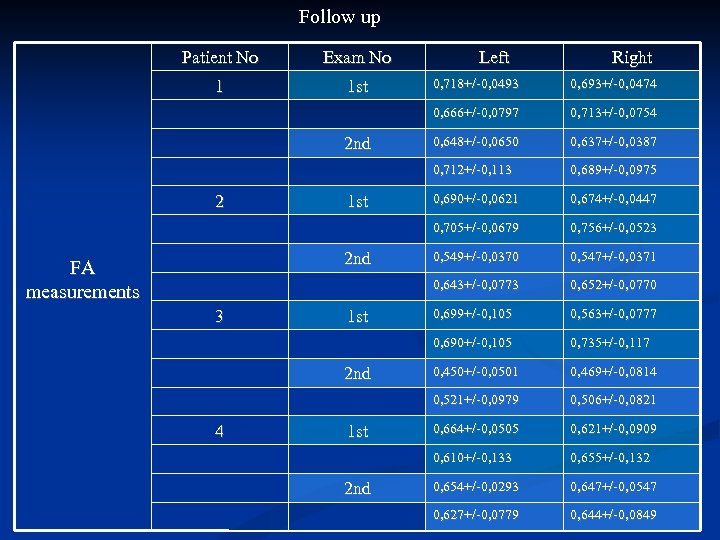

Comparing (FA) measurements, between controls and patients we found that FA measurements in patients were lower than in the age matched healthy subjects. A further decrease in FA measurements was also noticed with disease progression on the F/U study. Using fiber tractography we visualized the CST tract in healthy volunteers as well as ALS patients. A small number of patients, especially those with definite ALS, showed a visibly decreased volume of CST fibre bundles

Comparing (FA) measurements, between controls and patients we found that FA measurements in patients were lower than in the age matched healthy subjects. A further decrease in FA measurements was also noticed with disease progression on the F/U study. Using fiber tractography we visualized the CST tract in healthy volunteers as well as ALS patients. A small number of patients, especially those with definite ALS, showed a visibly decreased volume of CST fibre bundles

Follow up Patient No Exam No 1 1 st Left Right 4 1 st 2 nd 0, 674+/-0, 0447 0, 756+/-0, 0523 0, 549+/-0, 0370 0, 547+/-0, 0371 0, 652+/-0, 0770 0, 699+/-0, 105 0, 563+/-0, 0777 0, 735+/-0, 117 0, 450+/-0, 0501 0, 469+/-0, 0814 0, 506+/-0, 0821 0, 664+/-0, 0505 0, 621+/-0, 0909 0, 610+/-0, 133 2 nd 0, 690+/-0, 0621 0, 521+/-0, 0979 1 st 0, 689+/-0, 0975 0, 690+/-0, 105 3 0, 637+/-0, 0387 0, 643+/-0, 0773 2 nd FA measurements 0, 648+/-0, 0650 0, 705+/-0, 0679 1 st 0, 713+/-0, 0754 0, 712+/-0, 113 2 0, 693+/-0, 0474 0, 666+/-0, 0797 2 nd 0, 718+/-0, 0493 0, 655+/-0, 132 0, 654+/-0, 0293 0, 647+/-0, 0547 0, 627+/-0, 0779 0, 644+/-0, 0849

Follow up Patient No Exam No 1 1 st Left Right 4 1 st 2 nd 0, 674+/-0, 0447 0, 756+/-0, 0523 0, 549+/-0, 0370 0, 547+/-0, 0371 0, 652+/-0, 0770 0, 699+/-0, 105 0, 563+/-0, 0777 0, 735+/-0, 117 0, 450+/-0, 0501 0, 469+/-0, 0814 0, 506+/-0, 0821 0, 664+/-0, 0505 0, 621+/-0, 0909 0, 610+/-0, 133 2 nd 0, 690+/-0, 0621 0, 521+/-0, 0979 1 st 0, 689+/-0, 0975 0, 690+/-0, 105 3 0, 637+/-0, 0387 0, 643+/-0, 0773 2 nd FA measurements 0, 648+/-0, 0650 0, 705+/-0, 0679 1 st 0, 713+/-0, 0754 0, 712+/-0, 113 2 0, 693+/-0, 0474 0, 666+/-0, 0797 2 nd 0, 718+/-0, 0493 0, 655+/-0, 132 0, 654+/-0, 0293 0, 647+/-0, 0547 0, 627+/-0, 0779 0, 644+/-0, 0849